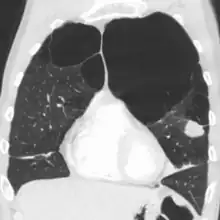

A chest X-ray and complete blood count may be useful to exclude other conditions at the time of diagnosis.[82] Characteristic signs on X-ray are hyperinflated lungs, a flattened diaphragm, increased retrosternal airspace, and bullae, while it can help exclude other lung diseases, such as pneumonia, pulmonary edema, or a pneumothorax.[83] A high-resolution CT scan of the chest may show the distribution of emphysema throughout the lungs and can also be useful to exclude other lung diseases.[25] Unless surgery is planned, however, this rarely affects management.[25] A saber-sheath trachea deformity may also be present.[84] An analysis of arterial blood is used to determine the need for oxygen; this is recommended in those with an FEV1 less than 35% predicted, those with a peripheral oxygen saturation less than 92%, and those with symptoms of congestive heart failure.[24] In areas of the world where alpha-1 antitrypsin deficiency is common, people with COPD (particularly those below the age of 45 and with emphysema affecting the lower parts of the lungs) should be considered for testing.[24]

Very severe emphysema with lung cancer on the left (CT scan)